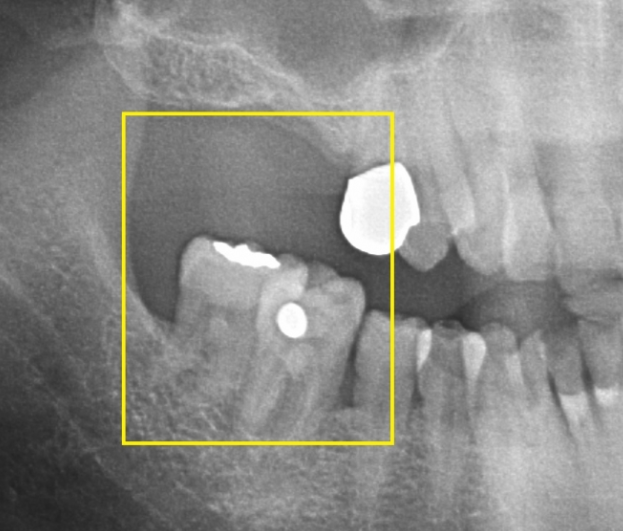

치아가 빠져 빈 공간이 생기게 되면 빠진 치아의 옆 치아 혹은 위아래로 맞닿는 치아가 그 빈 공간으로 이동하게 돼 치열이 망가지게 되면 틈이 생기고 음식물이 끼기 시작합니다. 음식물이 자주 끼게 되고 관리마저 잘되지 않으면 붓고 통증이 생깁니다.

백연화 교수는 "빈 공간을 지속적으로 방치하면 음식물을 씹는 것이 어렵게 돼, 소화 장애나 영양 부족 등 각종 전신적인 합병증을 유발할 수 있다"라며, "한 두 개의 치아가 빠져 지금 당장 불편감이 없다고 방치한다면 향후 치료를 받고자 할 때 추가적인 교정이나 보철치료 외에도 심한 경우 치아를 모두 발치해야 할 수도 있다"라고 전했습니다.

이어 백 교수는 "치료의 적기를 놓치면 멀쩡한 치아에 하지 않아도 됐을 치료를 하게 돼, 훨씬 더 큰 비용과 시간이 소요될 수 있고, 치료 결과도 좋지 않을 가능성이 높다"라며, "치아가 망가졌다면 가능한 한 빨리 치과 방문 후 적절한 치료를 받는 것이 필요하다"라고 조언했다고 합니다. 치아가 빠진 자리를 수복하는 방법에는 브릿지, 틀니 그리고 임플란트 등이 있습니다. 치아가 빠진 위치나 골상태, 주변 치아 상태 등에 따라 선택하게 되는 치료 방법은 달라집니다.

대표적인 치료 방법인 임플란트는 인공 뿌리를 심고 그 위에 치아 머리를 수복하는 것으로, 주변 치아의 손상 없이 구조를 복원할 수 있습니다. 임플란트 치료 기간은 발치 후 임플란트 심기 전까지의 대기시간과 임플란트를 심은 후 상부 보철물을 씌우기까지 대기시간에 따라 결정된다고 합니다. 전통적인 과정은 발치 후 3~4개월 정도를 기다려 치아의 뿌리가 있던 공간에 뼈가 어느 정도 차면, 임플란트를 심습니다. 이후 3개월 이상 기다려 뼈와 임플란트가 완전히 붙으면 보출물을 씌웁니다.